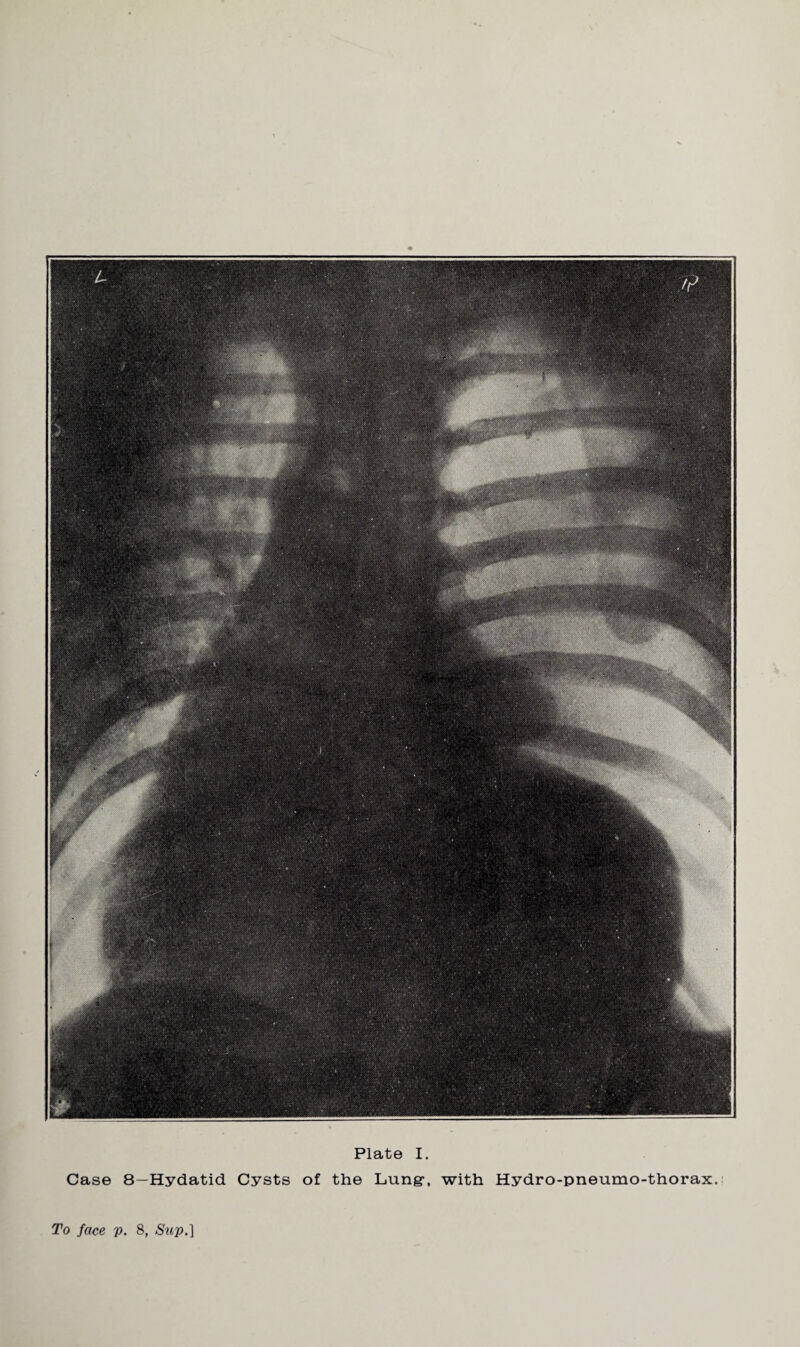

![Plate I. Case 8—Hydatid Cysts of the Lung-, with Hydro-pneumo-thorax. To face p. 8, Swp*]](https://iiif.wellcomecollection.org/image/b32156789_0011.jp2/full/800%2C/0/default.jpg)